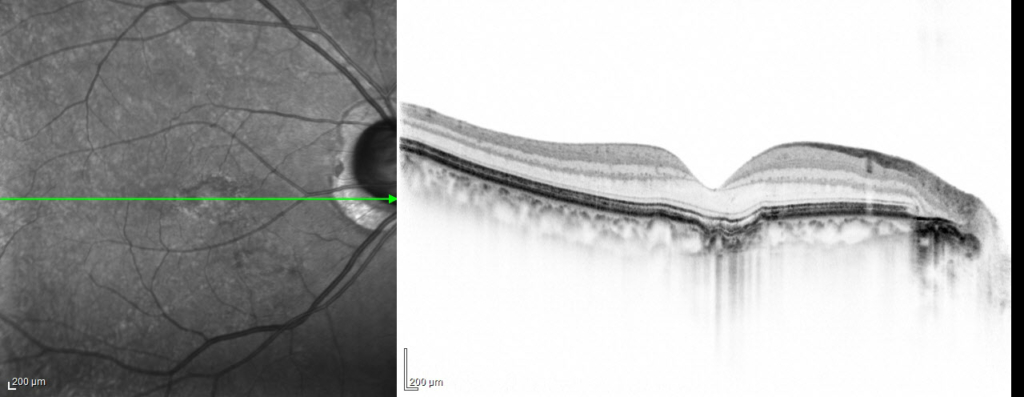

conforming typeとnon-conforming typeがあります。